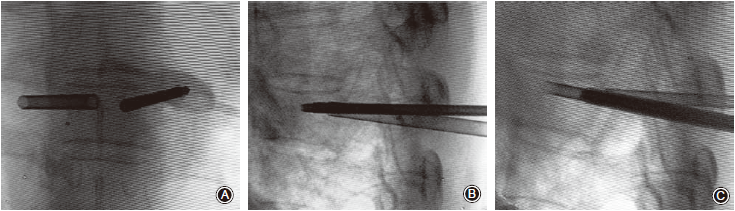

采用局部麻醉或全身麻醉,患者取俯卧位。首先采用“C”型臂或“O”型臂X线机透视定位,体表标记划线,经椎弓根穿刺逐步建立通道,抵达靶椎椎体,克式针引导下放置经特殊设计的金属空心套筒。套筒一直推进到椎体后部,再沿套筒内置入已经连接好主机的Intrabeam®针形放疗施用器,其内有与主机相连接的小型X射线发生器的治疗探头。“C”型臂或“O”型臂X线机正、侧位透视确认施用器位置,经放疗医生设计放疗范围和剂量,并与放疗物理师在工作站中确认后实施放疗。

术中放疗采用的Intrabeam®术中放疗仪利用10cm长、3.2cm外径的可移动球管内电子束,激发位于针形器尖端的金靶进而激发电磁辐射。理论上此电磁辐射在空间上具有各向同质性,即可认为是一个点放射源。脊椎IORT的常用剂量为距放射源5mm处表面8Gy的放疗剂量,放疗持续时间约4min。根据剂量学计算,估计在放疗针头的剂量约91Gy,而1 mm处剂量约为45Gy。因放疗剂量随着空间分布陡峭下降,在10mm外的周围组织,包括脊髓在内的重要组织其放疗剂量均足够小且安全;同时对于操作者也无辐射损害(图1,2)。